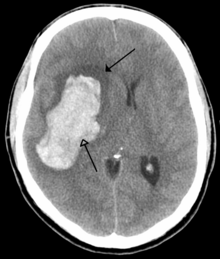

CT scan of an intraparenchymal bleed (bottom arrow) with surrounding edema (top arrow)

There are two main types of hemorrhagic stroke:[28][29]

The above two main types of hemorrhagic stroke are also two different forms of intracranial hemorrhage, which is the accumulation of blood anywhere within the cranial vault; but the other forms of intracranial hemorrhage, such as epidural hematoma (bleeding between the skull and the dura mater, which is the thick outermost layer of the meninges that surround the brain) and subdural hematoma (bleeding in the subdural space), are not considered "hemorrhagic strokes".[30]

Hemorrhagic strokes may occur on the background of alterations to the blood vessels in the brain, such as cerebral amyloid angiopathy, cerebral arteriovenous malformation and an intracranial aneurysm, which can cause intraparenchymal or subarachnoid hemorrhage.[citation needed]